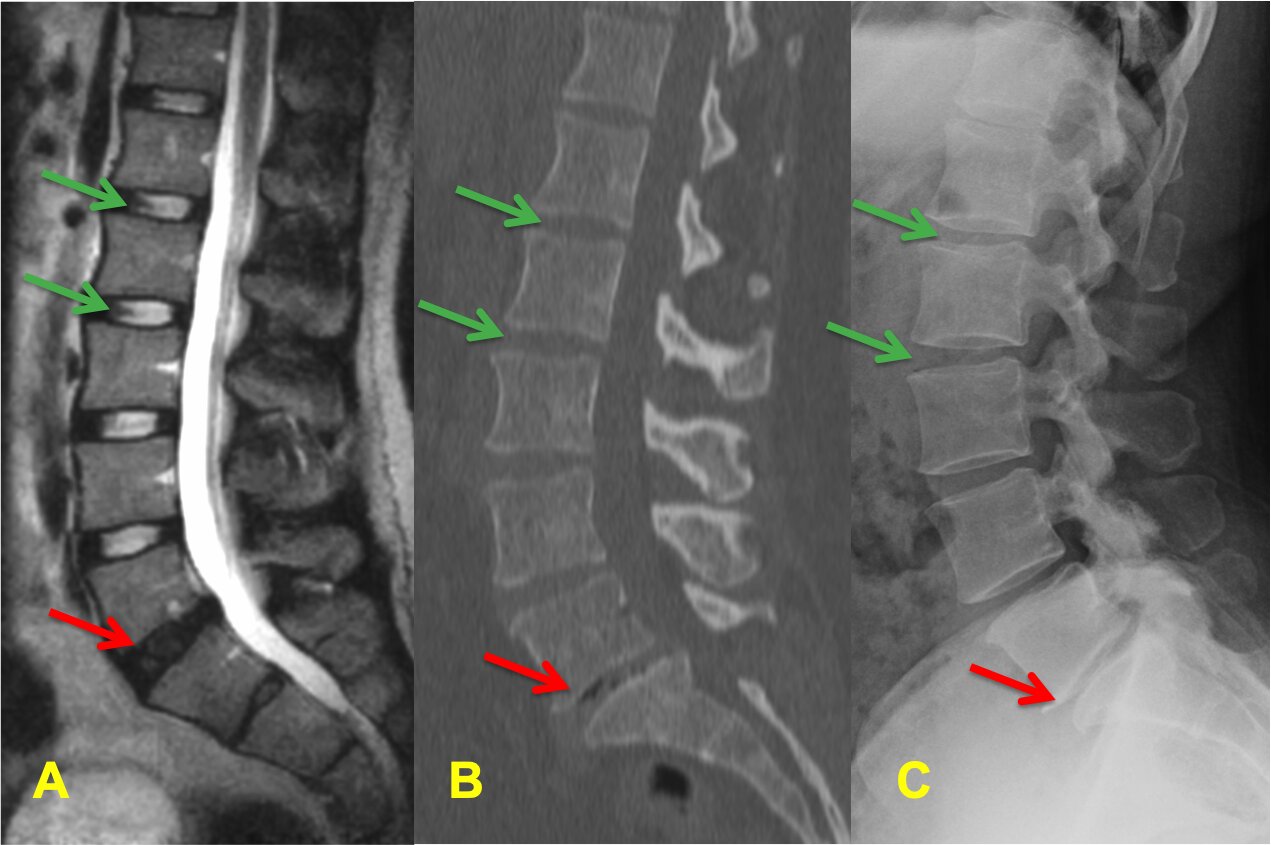

The spine is made of vertebrae, intervertebral discs, facet joints, ligaments, and nerves. Discs act as shock absorbers, while facet joints guide movement. When discs lose hydration or joints become overloaded, degenerative conditions begin to develop.

A herniated disc occurs when the inner disc material pushes through a tear in the outer disc wall. This can place pressure on spinal nerves and cause severe symptoms.

A bulging disc is an early form of disc degeneration where the disc extends outward but has not ruptured. Although often considered “less serious,” bulging discs can still irritate nerves and restrict movement.

Degenerative Disc Disease (DDD or DJD) occurs as discs lose hydration, elasticity, and height over time. This increases spinal instability and joint stress.

Osteoarthritis affects the facet joints of the spine when cartilage breaks down over time. This leads to inflammation, stiffness, and sometimes bone spur formation.

Spinal arthritis often develops secondary to disc degeneration, not independently.

Why These Conditions Commonly Occur Together

Patients rarely have just one diagnosis. A typical progression looks like:

- Disc dehydration

- Bulging disc

- Herniated disc

- Joint overload

- Osteoarthritis